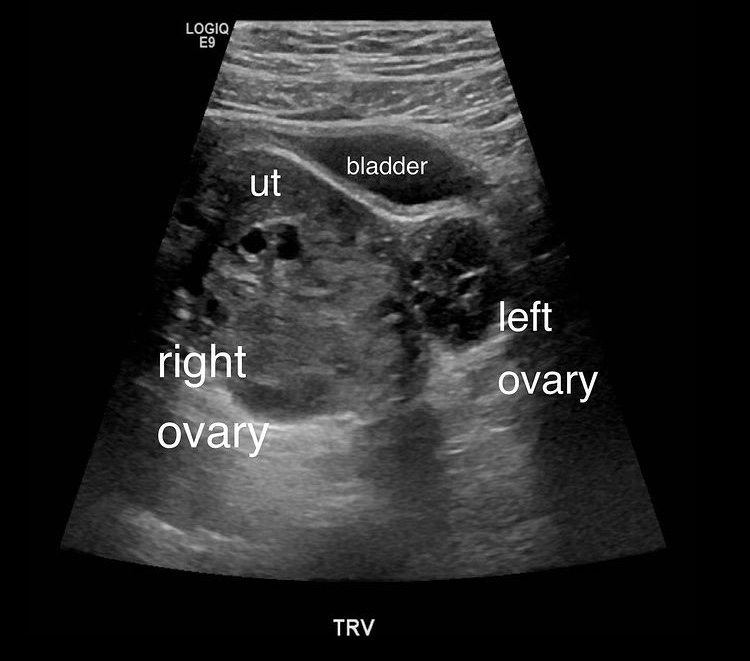

Ultrasound usually shows an enlarged ovary with peripherally displaced follicles, free fluid is often present, no Doppler flow is also often seen (early torsion can still have arterial flow, with venous and lymphatic drainage absent, also the ovary may spontaneously detorse).

Sonographic findings

- Unilaterally enlarged ovary

- Peripherally displaced follicles due to edema

- Coexistent mass

- Twisted pedicle (not always seen)

- Free fluid